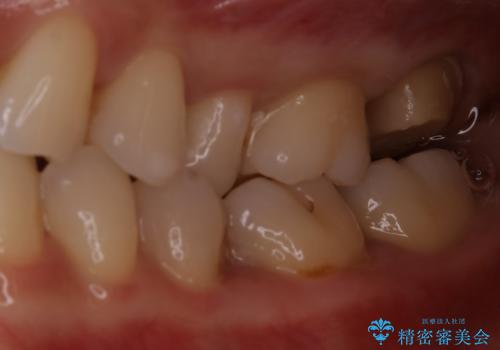

- 一番奥の歯に違和感がありご来院頂いた患者様です。

診断の結果、一番奥の歯は失活していたため精密根管治療から治療介入となりました。奥から2番目の歯にも大きな虫歯が認められたため、セラミックインレーによる補綴治療を行いました。 精密根管治療は患者様のご希望により、福本院長に行っていただきました。